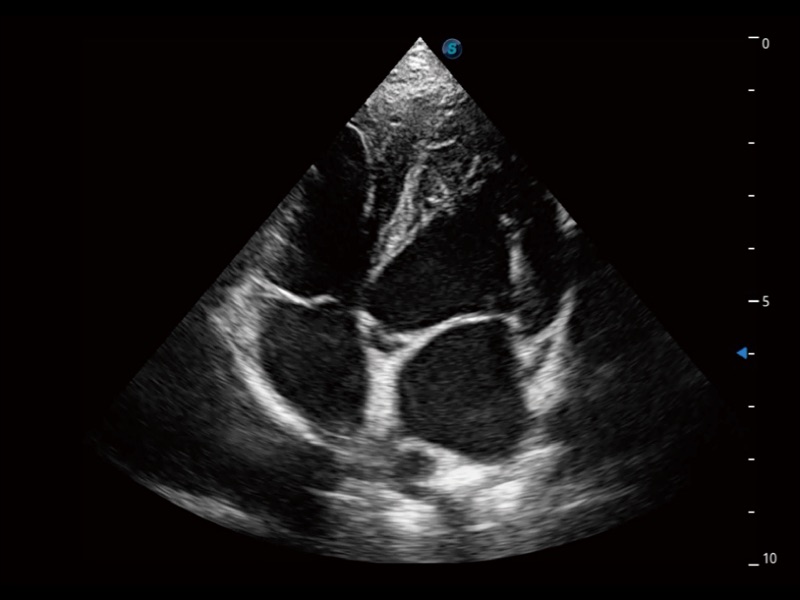

大型犬、马科、农场动物及大型异宠动物

ProPet 70专为动物医生设计,对不同的动物体型和生理结构作出了针对性的优化。通过动物影像专用软件,可满足个性化的应用需求,帮助动物医生获得更精确的诊断数据。

ProPet 70 全新的动物超声智能软件和丰富的探头群,为动物医生提供了高清晰度和精细分辨率的图像,无论在宠物、马科、畜牧还是实验室动物等应用中都可以轻松应对,为您的日常工作带来满意的体验。